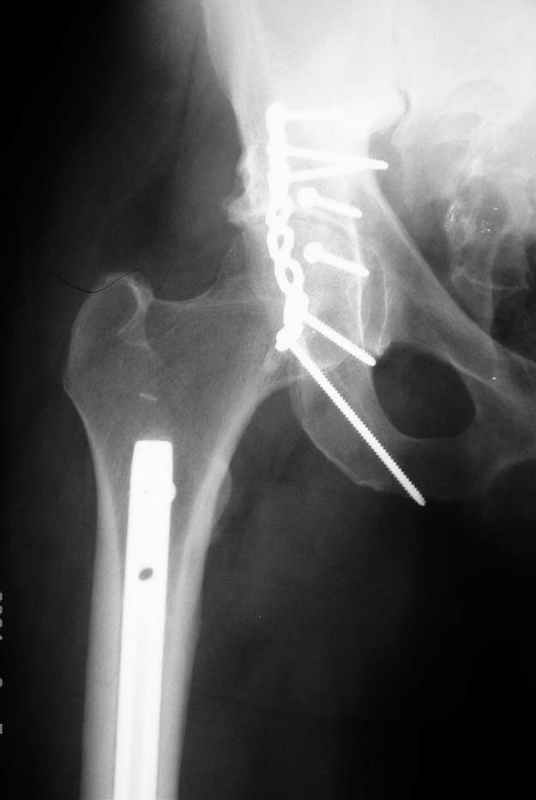

Не дождавшись советов, в понедельник прооперировал больного, заняло времени..., но все сделал в один этап: сначала фиксировал ипсилатеральный перелом бедра и шейки реконструктивным гвоздем Smith&Nephews, потом из расширенного илеофеморального доступа фиксировал перелом крыла подвздошной кости тягловым винтом, нейтрализующей пластиной заднюю колонну, и тягловыми винтами 3,5 мм переднюю колонну.

Несмотря на расширенный доступ, особой кровопотери не было, перелил только одну дозу эр.массы и на утро Нв- 10.5 и как ни странно больной не жалуется на сильные боли и стопа не *висит*, хотя при интраоперационной ревизии седалищного нерва обширная гематома в периневральной оболочке.

К сожалению, набора для ретроградного или антеградного реконструктивного штифтования в операционной нет, поэтому доставка заняла н-ное время. Вопрос, который возник у меня- по поводу оптимальной тактики хирургии: вся фиксация в один этап из расширенного доступа или последовательно сначала бедро и позже реконструкция впадины, комбинированный доступ к впадине отдельно к передней и задней колоннам или из расширенного илеофеморального одного доступа. Все-таки решил остановиться на одноэтапном подходе и спустя 5 дней (как раз и наборы привезли) из расширенного илеофеморального доступа сначала фиксировал реконструктивным штифтом Smith&Nephews бедро и

шейку (благо перелом шейки 2 типа -относительно стабильный) затем фрагмент крыла подвздошной кости Lag screw, далее пластина на заднюю колонну и винты в переднюю колонну.(с размерами и направлением винтов ошибка вышла:-((, но интраоперационно у меня была полная уверенность , что винты *ушли* в лонную кость).

Еще раз спасибо за комментарии и готовность помочь с имплантами. Постоп картинки в приложении,